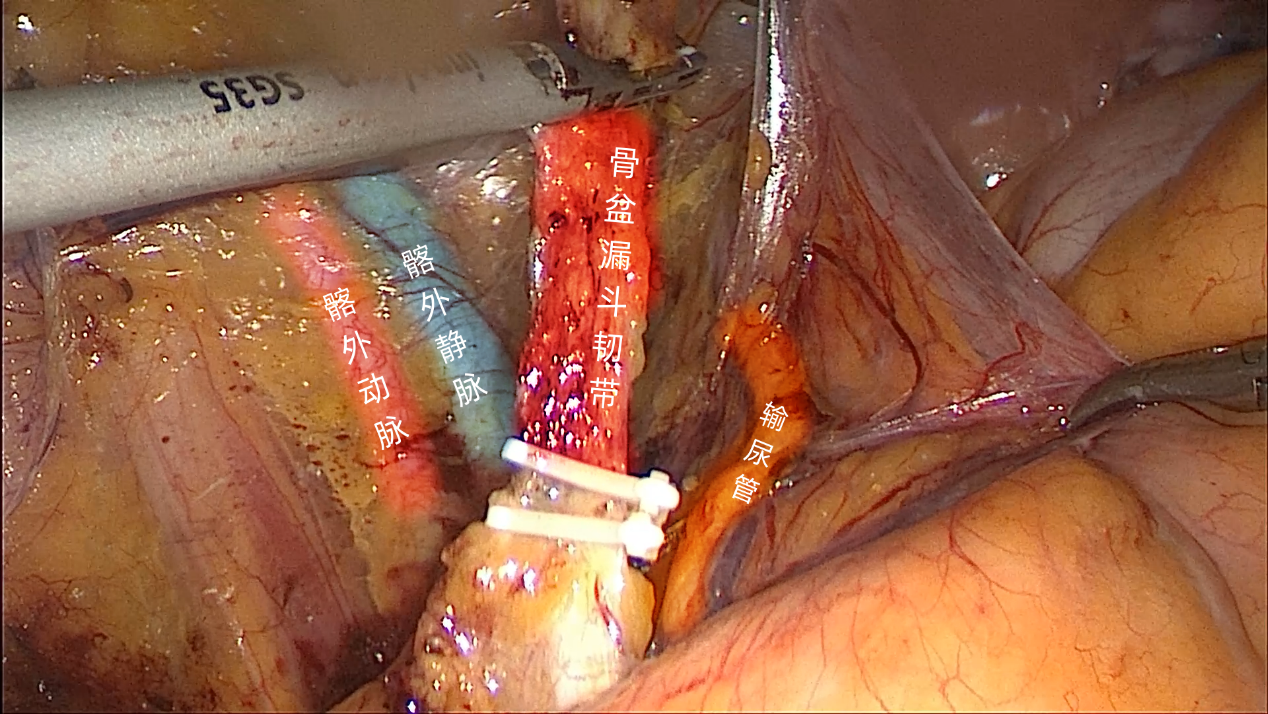

2.2 打开骨盆漏斗韧带的内侧腹膜(外侧腹膜在游离输尿管时已打开),游离骨盆漏斗韧带。(图6)

图6

2.3 切断骨盆漏斗韧带时,可选择使用Ham-lock夹闭后切断,相对更加牢固;也可选择双极电凝后切断。(图7)

图7

因为此前已游离输尿管,这些操作均在直视输尿管的情况下完成,这样可以最大程度上保证“VIP”安全。